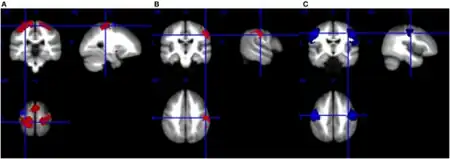

- Magnetic resonance imaging (MRI): An MRI of the brain and spinal cord is recommended in patients with UMN signs and symptoms to explore other causes, such as a tumor, inflammation, or lack of blood supply (stroke).[14]